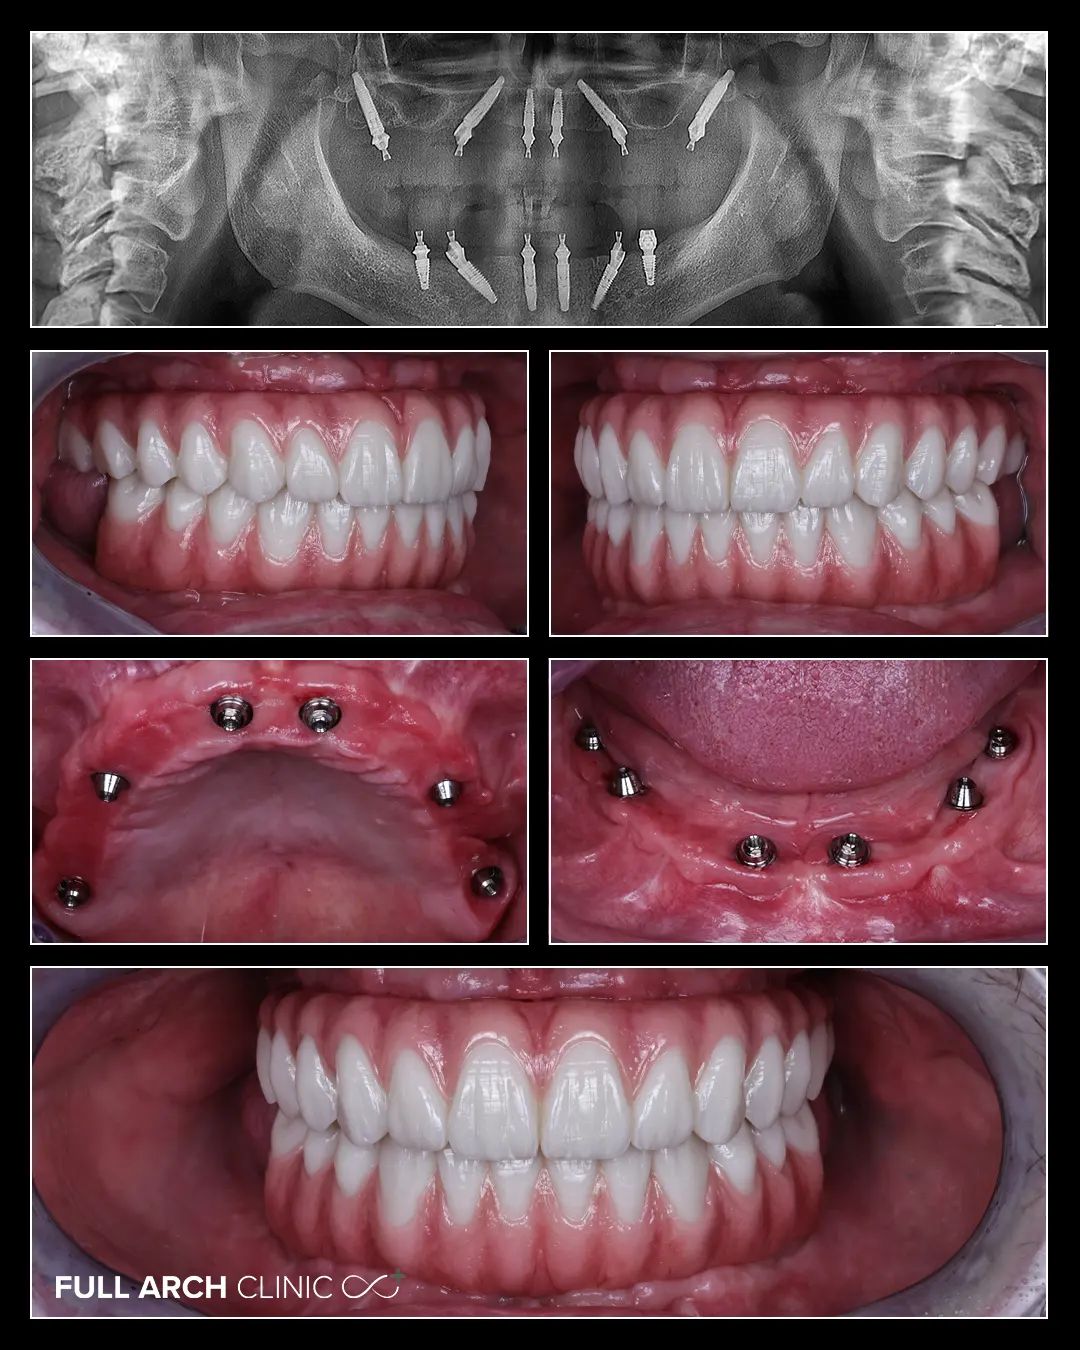

Dantura Fixa pe 12 implanturi dentare - maxilar si mandibula

thumbnail pacient cu dantura fixa pe 12 implanturi

Domnul din imagini s-a prezentat cu o afectare parodontala generalizata, cu dinti mobile si dureri la masticatie.

Singura lui dorinta a fost sa il ajutam cu refacerea maxilarelor pe rand si nu in acelasi timp.

Tratamentul in cazul dansului a constat in extractii complete si o reabilitare cu 6 implanturi atat la maxilar cat si la mandibula.

Initial am realizat interventia la maxilar si i-am oferit domnului o lucrare provizorie a II-a zi.

Am continuat tratamentul si cu partea mandibulara la aproximativ 3 luni de la inceperea acestuia.

Iar la 6 luni de la finalizarea arcadei inferioare, am realizat lucrarile finale din ceramica stratificata pe zirconiu.

Ceramica stratificata ne ajuta sa oferim efecte extrem de naturale gingiei si sa o apropiem cat mai mult de forma si culoarea gingiei naturale.

In imagini se poate vedea vindecarea perfecta a gingiei pacientului la aproximativ 9 luni de la inceperea tratamentului, acesta fiind un element cheie pentru stabilitatea tratamentului pe termen lung.